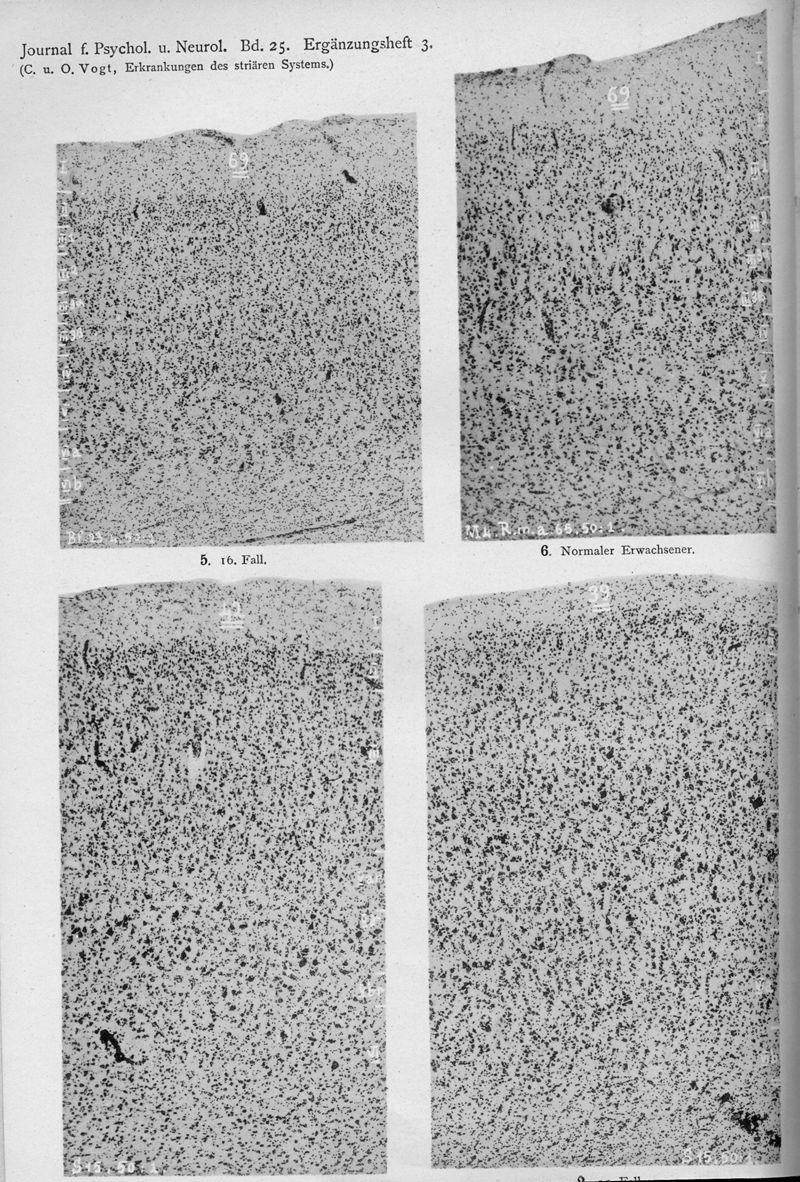

VOGT, Cécile / VOGT, O.

In : Journal für Psychologie und Neurologie,

1920, Vol. 25, pp. 627-846